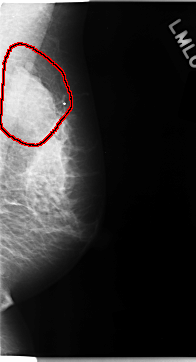

FILE: C_0113_1.LEFT_MLO.OVERLAY

TOTAL_ABNORMALITIES 1

ABNORMALITY 1

LESION_TYPE MASS SHAPE LOBULATED MARGINS MICROLOBULATED

ASSESSMENT 5

SUBTLETY 5

PATHOLOGY MALIGNANT

TOTAL_OUTLINES 1

BOUNDARY